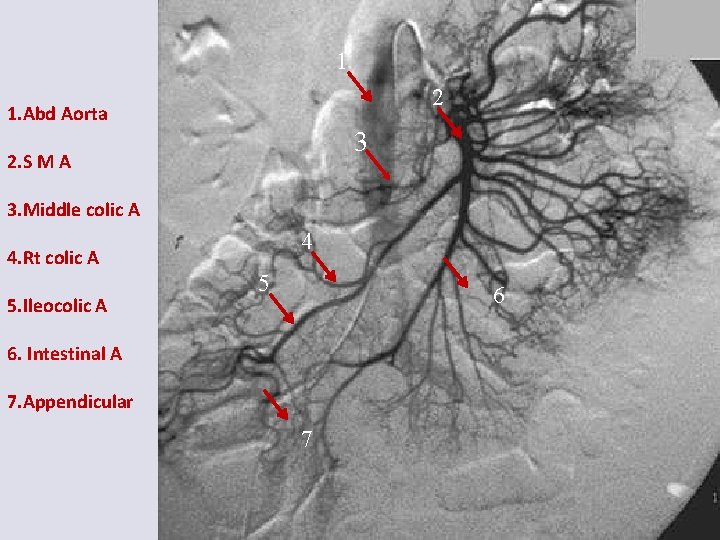

1 2 1. Abd Aorta 3 2. S M A 3. Middle colic A 4 4. Rt colic A 5. Ileocolic A 5 6 6. Intestinal A 7. Appendicular 7